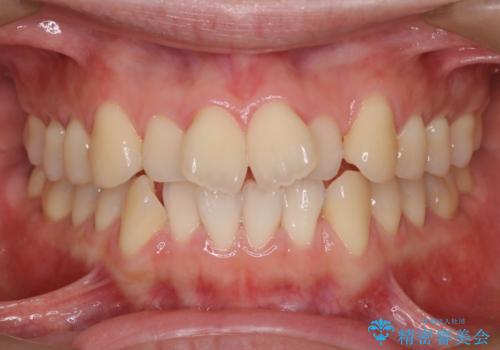

- インビザラインで非抜歯治療を行いました。IPRと拡大をし、叢生、咬合をきれいにしました。

主訴であったかみ合わせを正しい位置に動かし、バランスよくかめるようになりました。矯正治療終了後にメタルインレーをセラミックインレーに替えました。